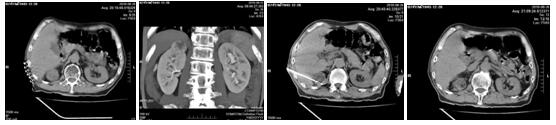

化疗后病人一般情况尚可,经过充分的术前检查及准备后,2018年6月26日在苗满园主任的带领下,与CT室联合进行手术,局麻后在CT引导下将电极针准确插入肿瘤内部,对肿瘤实施微波消融术。仅20分钟顺利完成手术,达到了预期的满意效果和消融范围。术中患者清醒无不适,术后6个小时患者即可下床活动。术后评估微波消融治疗范围,无出血及邻近脏器损伤。